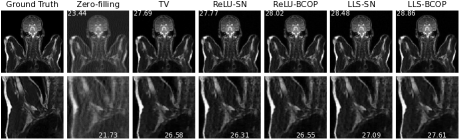

Section 5 is devoted to the application of our framework to the problem of biomedical image reconstruction. Our approach revolves around the design of a robust 111-Lipschitz CNN for image denoising that mimics the architecture of DnCNN ZZCMZ2017 —a very popular image denoiser. The important twist is that, unlike DnCNN, the convolution layers of our network are constrained to be Parseval, which makes our denoiser compatible with the powerful plug-and-play (PnP) paradigm for the resolution of linear inverse problems Chan2016plug ; Kamilov2023plug ; Sun2021 ; Venkatakrishnan2013plug . We first provide mathematical support for this procedure in the form of convergence guarantees and stability bounds. We then demonstrate the feasibility of the approach for MRI reconstruction and report experimental results where it significantly outperforms the standard technique (total-variation-regularized reconstruction) used in compressed sensing.